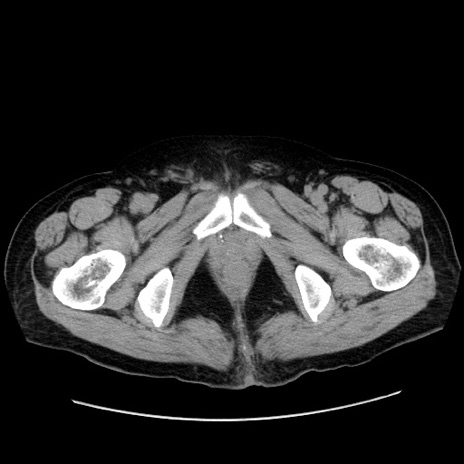

症例30(横断像)

【症例】80歳代男性

【主訴】臍周囲痛

【現病歴】約6時間前から臍下部痛が出現。次第に腹部膨隆・背部痛も生じてきたため来院。背部痛の場所は変化しない。

【身体所見】意識清明、BT 36.3℃、BP  131/87mmHg、P 87bpm、SpO2 100%(RA)、臍周囲自発痛・圧痛あり、反跳痛なし、自発痛部位に一致して板状硬あり、腹部膨隆、腸雑音減弱、CVA tenderness両側陰性。